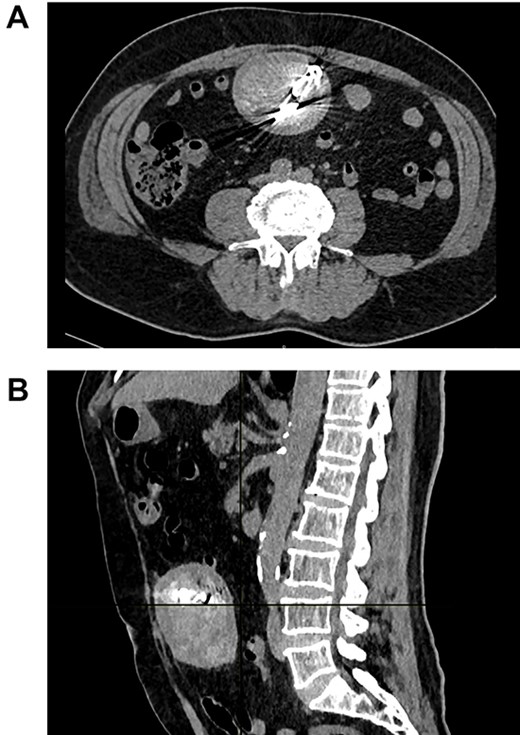

Surprisingly, a well-encapsulated 7.2 × 6.3 × 8.6 cm spongiform mass with rounded edges and multiple radiodense linear calcifications on its center was discovered inside his abdomen (Fig. 1A and B).

(A) CT the mass is seen in the abdomen with radiopaque material on its center. (B) CT the mass attached to the bowel.